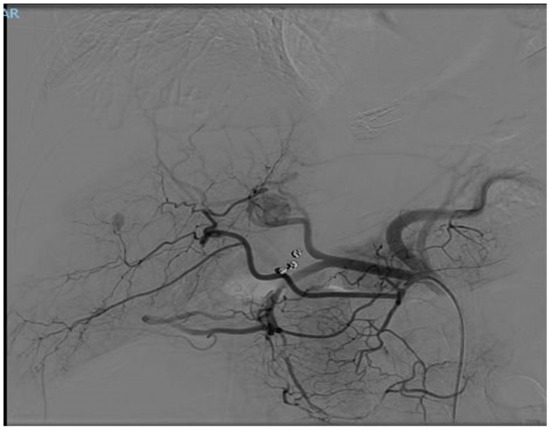

In December 2023, a full-body CT scan revealed that two known liver metastases had grown, and a new lesion had appeared near the inferior vena cava (IVC) in the liver. A multi-phase liver CT protocol performed later in December identified five lesions in the right liver lobe and at least one lesion in the left lobe (Figure 1). After consultation with an interventional radiologist, it was determined that the disease spread pattern was unsuitable for chemoembolization. Still, it was appropriate for selective internal radiation therapy (SIRT) using Yttrium-90. In February 2024, approximately one week before SIRT treatment, the patient underwent preparatory hepatic catheterization and selective simulation using Tc-99mma, demonstrating the feeding arteries to the liver tumors, and a low lung shunt fraction of 9% was calculated. During this preparatory hepatic catheterization simulation, the arteries feeding the tumors were mapped, allowing optimal catheter location placement (Figure 2). On 8 February 2024, the SIRT procedure was conducted under general anesthesia due to the patient’s back pain and inability to lie flat; a puncture was performed under local anesthesia, with fluoroscopy and ultrasound guidance, in the right common femoral artery. Catheterization of the superior mesenteric artery (SMA) was performed, and pressure injection showed no vessels from the SMA supplying the tumor. Subsequently, catheterization of the celiac artery was performed, with automatic injection showing celiac artery anatomy and pathological tumor enhancement in both liver lobes, particularly in the right lobe. A branch from the common hepatic artery was identified, supplying part of the right liver lobe, including at least two tumors. An accessory branch to the left lobe was observed through the left gastric artery, though it did not supply the liver tumors. Three doses of technetium were injected selectively into the right hepatic artery distal to the cystic artery, the left hepatic artery and a branch supplying part of the tumors in the right lobe, which originates from the proximal common hepatic artery. Due to the proximity of the origin of the right gastric artery, embolization with 2 mm coils was performed. At the end of the scan, the patient was transferred to the Nuclear Medicine Department, which showed a minimal lung shunt (9%) with no evidence of gastrointestinal shunt. The patient was then returned to the angiography suite for the second phase of the procedure. Selective catheterization of the three arteries was repeated, and technetium was injected with a total calculated dose of 1.4 GBq (0.4 to the left lobe, 0.4 to the systolic artery in the right lobe, and 0.5 to the right hepatic artery distal to the cystic artery). SIRT treatment was performed successfully with no apparent complications, and the patient was discharged home the next day.

Figure 2.

This CT angiography, performed on 8 February 2024, simulates contrast injection, highlighting the blood supply to the tumors during the arterial phase.